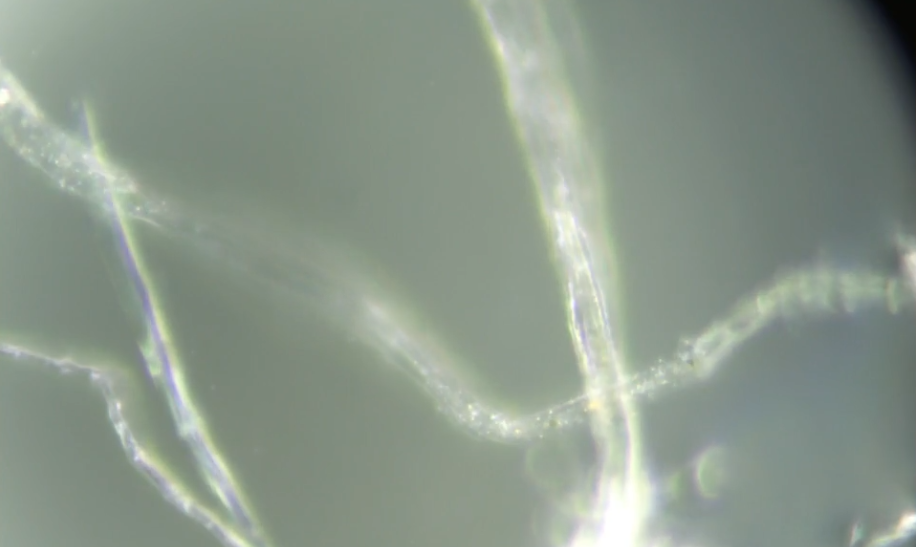

Vainqueur du Vendée Globe en janvier dernier, Charlie Dalin a dévoilé mercredi être atteint depuis 2023 d’une forme rare de cancer : une tumeur stromale gastro-intestinale, ou GIST (gastrointestinal stromal tumor). Ces tumeurs se développent à partir des cellules de Cajal, des cellules « pacemaker » du tube digestif. « Ces cellules déclenchent les ondes péristaltiques, qui font avancer les aliments dans le système digestif. Elles sont situées sur la couche externe du tube, ce qui explique la rareté de ce cancer », détaille le Dr Marc Pracht, oncologue et vice-président du Centre Eugène Marquis, principal établissement de santé dans la lutte contre le cancer en Bretagne. La GIST n’est pas un cancer évitable. « On ne connaît pas de facteur de risque, sauf de très rares formes familiales », rappelle le médecin.